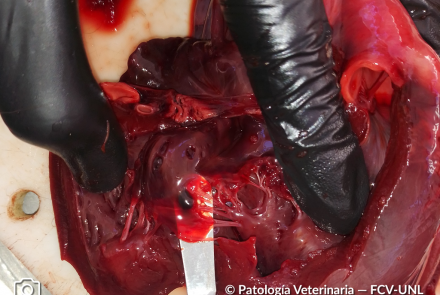

Quiste hemático subendocárdico

Se observa una cavidad quística circunscripta con contenido sanguinolento (quiste hemático) subendocardico en válvula

tricúspide auriculo ventricular derecha.

Especie: Bovino, 1 semana de vida.